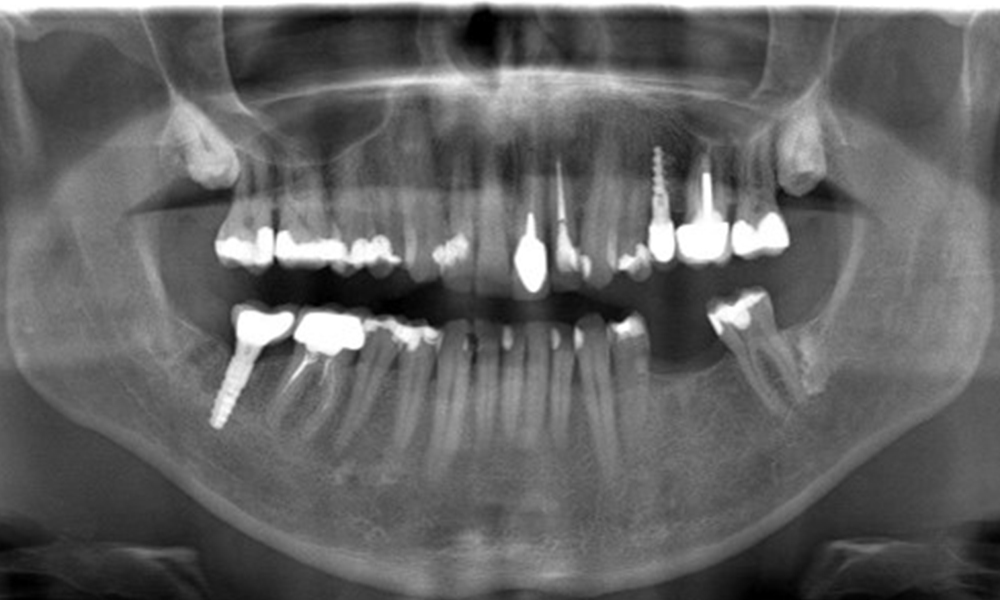

OPG: 29/02/2024

The X-ray image shows the bone loss

The X-ray images show the bone loss.